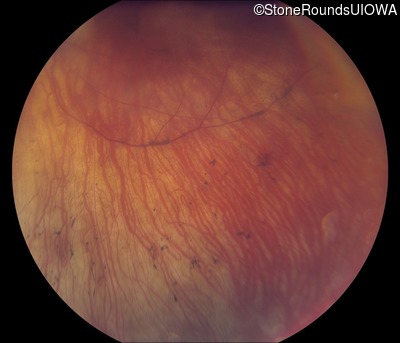

Fundus Photography - Right - 20/200 +2

Exemplar